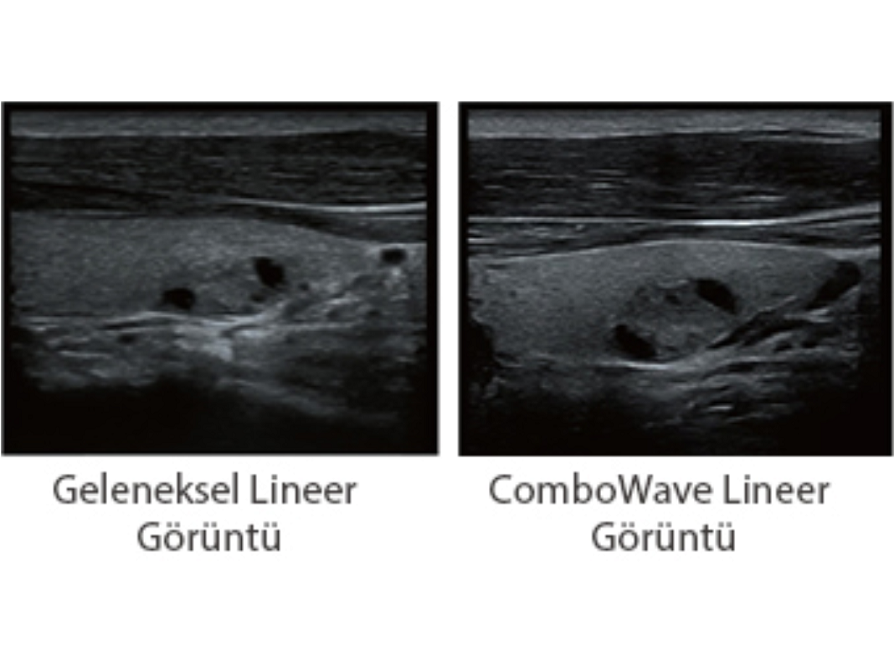

ComboWave d?nÞ?tÞrÞcÞler

Geleneksel d?nÞ?tÞrÞcÞler ile kar??la?t?r?ld???nda ComboWave d?nÞ?tÞrÞcÞlerin, akustik spektrumu ?nemli ?l?Þde optimize etmek ve akustik empedans? azaltmak i?in yeni bir kompozit piezoelektrik materyal tÞrÞnÞ kulland?klar? g?rÞlÞr. Mindray'in benzersiz 3T teknolojisi ile entegre edilen ComboWave lineer d?nÞ?tÞrÞcÞler, tiroid, meme, vaskÞler ve daha fazla alanda yÞksek g?rÞntÞ ??zÞnÞrlÞ?Þ ve tekdÞzeli?i ile ÞstÞn performans? deneyimlemenizi sa?lar.